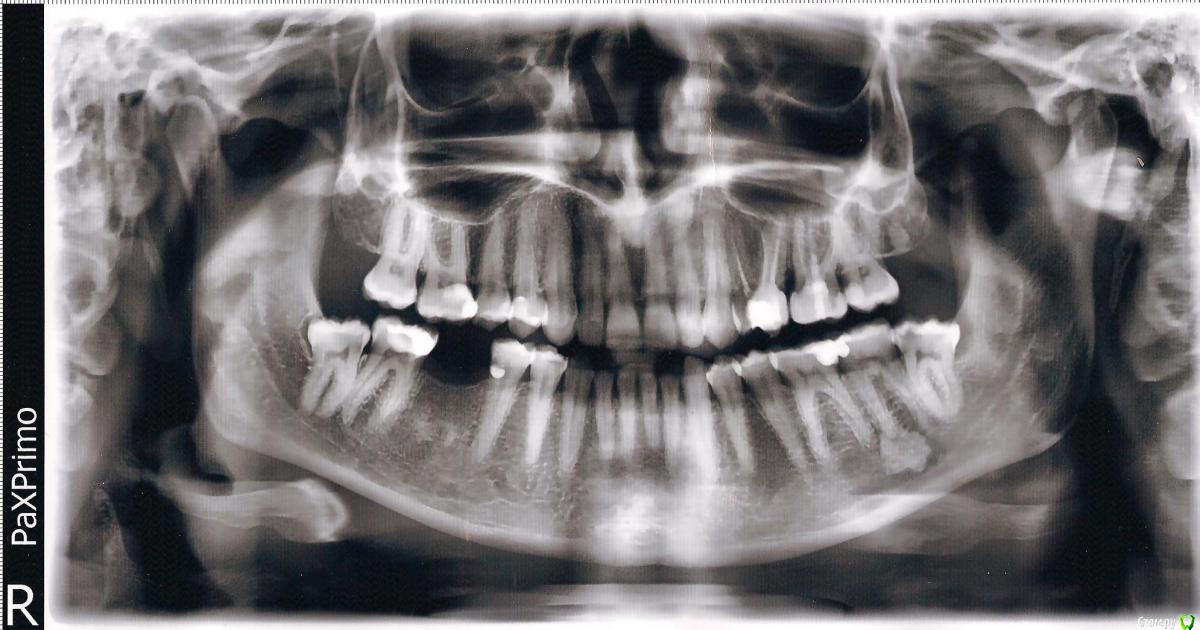

Ольга* Опубликовано 17 марта, 2015 Поделиться Опубликовано 17 марта, 2015 (изменено) Скажите пожалуйста, как удалить зуб мудрости при дисфункции внчс. Рот до конца не открывается, зуб полностью не вырос. Где лучше удалять и каким способом? Зуб с правой стороны. Изменено 17 марта, 2015 пользователем Ольга* Ссылка на комментарий

Ольга* Опубликовано 17 марта, 2015 Автор Поделиться Опубликовано 17 марта, 2015 (изменено) Меня больше интересуют последствия для суставов. Могут быть осложения и как их избежать? Зуб практически полностью в десне,к тому же там всё опухло. Его распиливать нужно или можно целиком удалить? А что это за прикусной блок и для чего он нужен? Изменено 17 марта, 2015 пользователем Ольга* Ссылка на комментарий